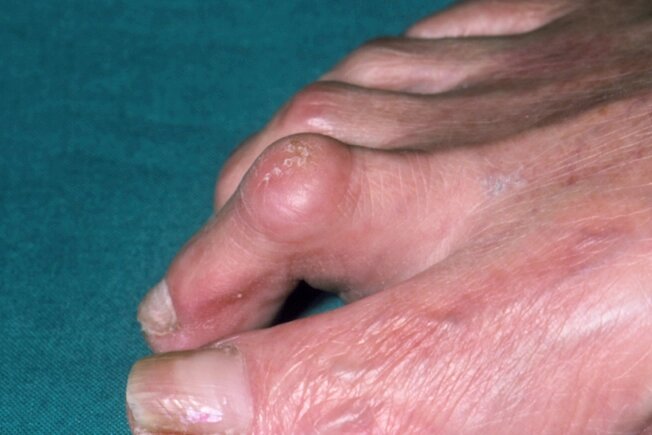

Deformarea degetului în ciocan

Aceasta este o îndoire anormală a articulațiilor mijlocii ale degetului de la picioare. Acesta este de obicei „al doilea” deget, lângă degetul mare. Dar această afecțiune poate afecta și degetul al treilea, al patrulea și al cincilea. Veți observa o deformare neobișnuită și este posibil să aveți ceva dureri când vă mișcați, precum și calusuri de la pantofi. Medicul dumneavoastră poate trata acest tip de deformare cu pantofi speciali, medicamente pentru durere și, uneori, intervenții chirurgicale.